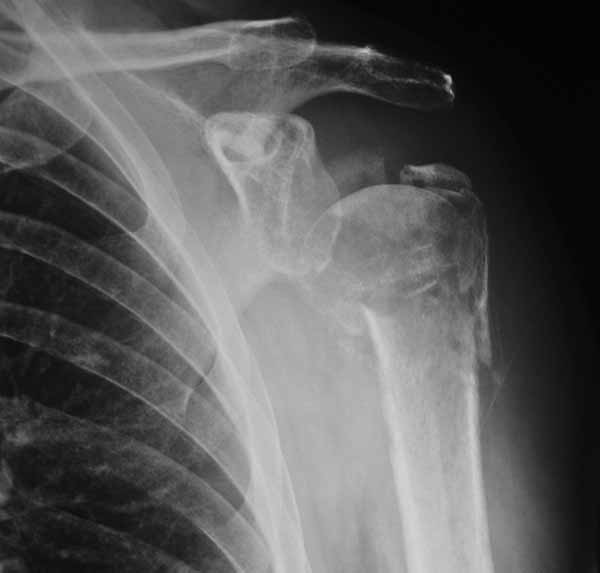

49 yo male RHD architect 3 mos s/p left prox humerus fx/dislocation in MCA presented today wanting know if he had any other treatment options at this time. He had initial PP, which was better reduced, but fell back into valgus impaction. He has 45 degrees FF, 40 degrees Abduction, 20 degrees ER of motion now w/ limited function.

Anyone consider ORIF and use Norian as reported for acute valgus impacted fx in Sept JBJS, Hemiarthroplasty or leave it alone?

I assume MCA is MVA representing high energy injury.

Thanks. MCA is mororcycle accident. I am sure he had a slight neurologic injury as he had an inferior dislocation (subluxio erectae) He nicely describes his arm stuck up over his head. He states his axillary sensation is normal now.

My vote is hemiarthroplasty if it is painful, nothing if it is not. I would not be optimistic about improving motion.

It's hard to tell from the xrays exactly how thin the head fragment is but I wonder if you were able to get screws right up to the subchondral bone, backfilling the impacted area well with bone graft, and be a little more protective, if you wouldn't be able to get it to heal. I think that a hemiarthroplasty, while certainly a reasonable choice, burns another bridge. Tough case for sure.